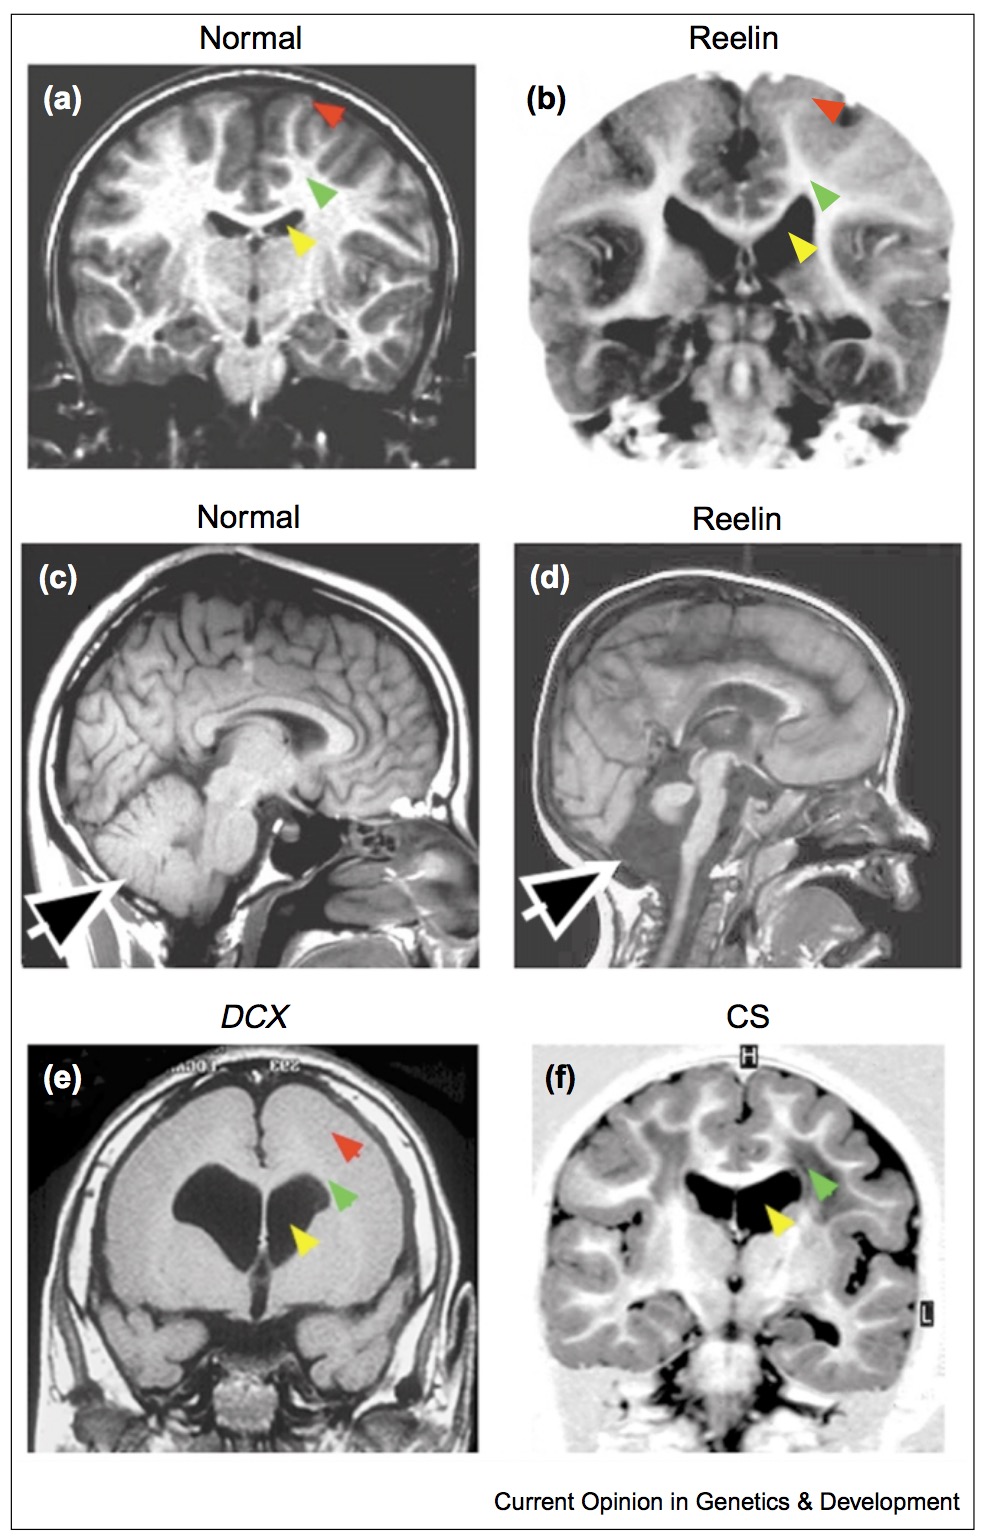

Defects in cortical development

- lissencephaly: smooth brain

- do not have characteristic gyri patterns

- leads to death, severe epilepsies and mental retardation

- cause is defects in neural migration during development

Note:

Gyrification from constrained cortical expansion

[^Tallinen:2014] http://dx.doi.org/10.1038/nphys3632